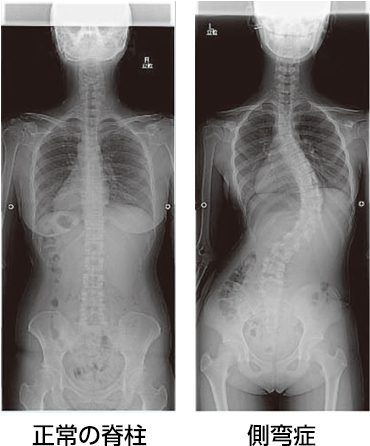

側弯症 軽度 見た目 (307 無料画像)

第1回 脊柱側弯症について脊椎手術.com。

特発性側弯症。

側弯症KOMPAS – 慶應義塾大学病院 医療・健康情報サイト。

側弯症とは?軽度は気づきにくい?原因やセルフチェック法など 医師解説LITALICO発達ナビ。

側弯症。